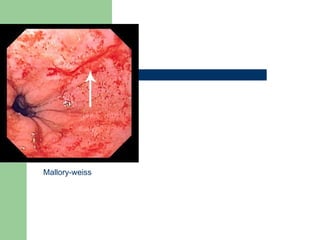

Mucosal tear (Mallory-Weiss) Esophagogastric mucosal tear Initially the patient has  vomiting without  blood. Continued emesis leads to pain from the  tear  and eventually the patient develops  hematemesis .

Mucosal tear (Mallory-Weiss)Esophagogastric mucosal tear Initially the patient has vomiting without blood. Continued emesis leads to pain from the tear and eventually the patient develops hematemesis .